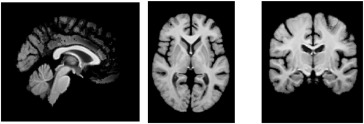

图4. 通过对训练数据中前100名受试者进行平均来构建模板。上图:通过平均获得的强度模板。下图:与平均强度模板对应的标签图。通过平均构建的模板明显不如AtlasMorph模板清晰。